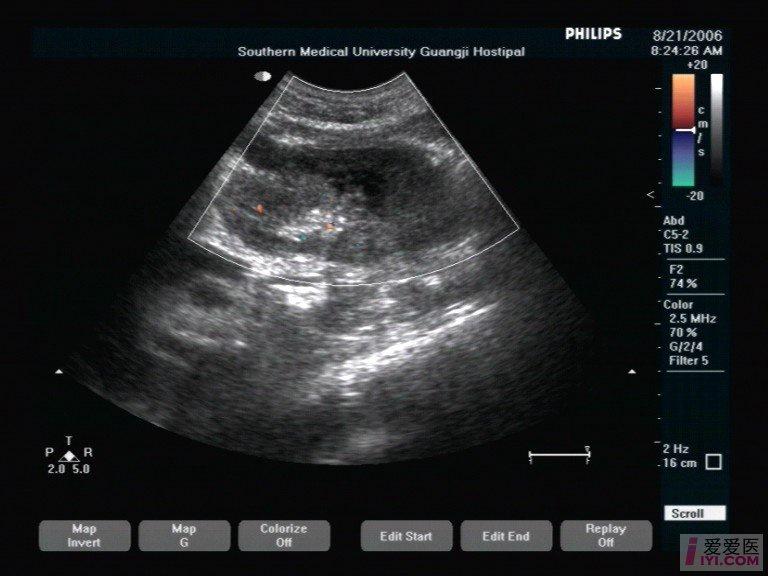

肾脏挫裂伤 - 超声医学讨论版 - 爱爱医医学论坛

图片尺寸768x576